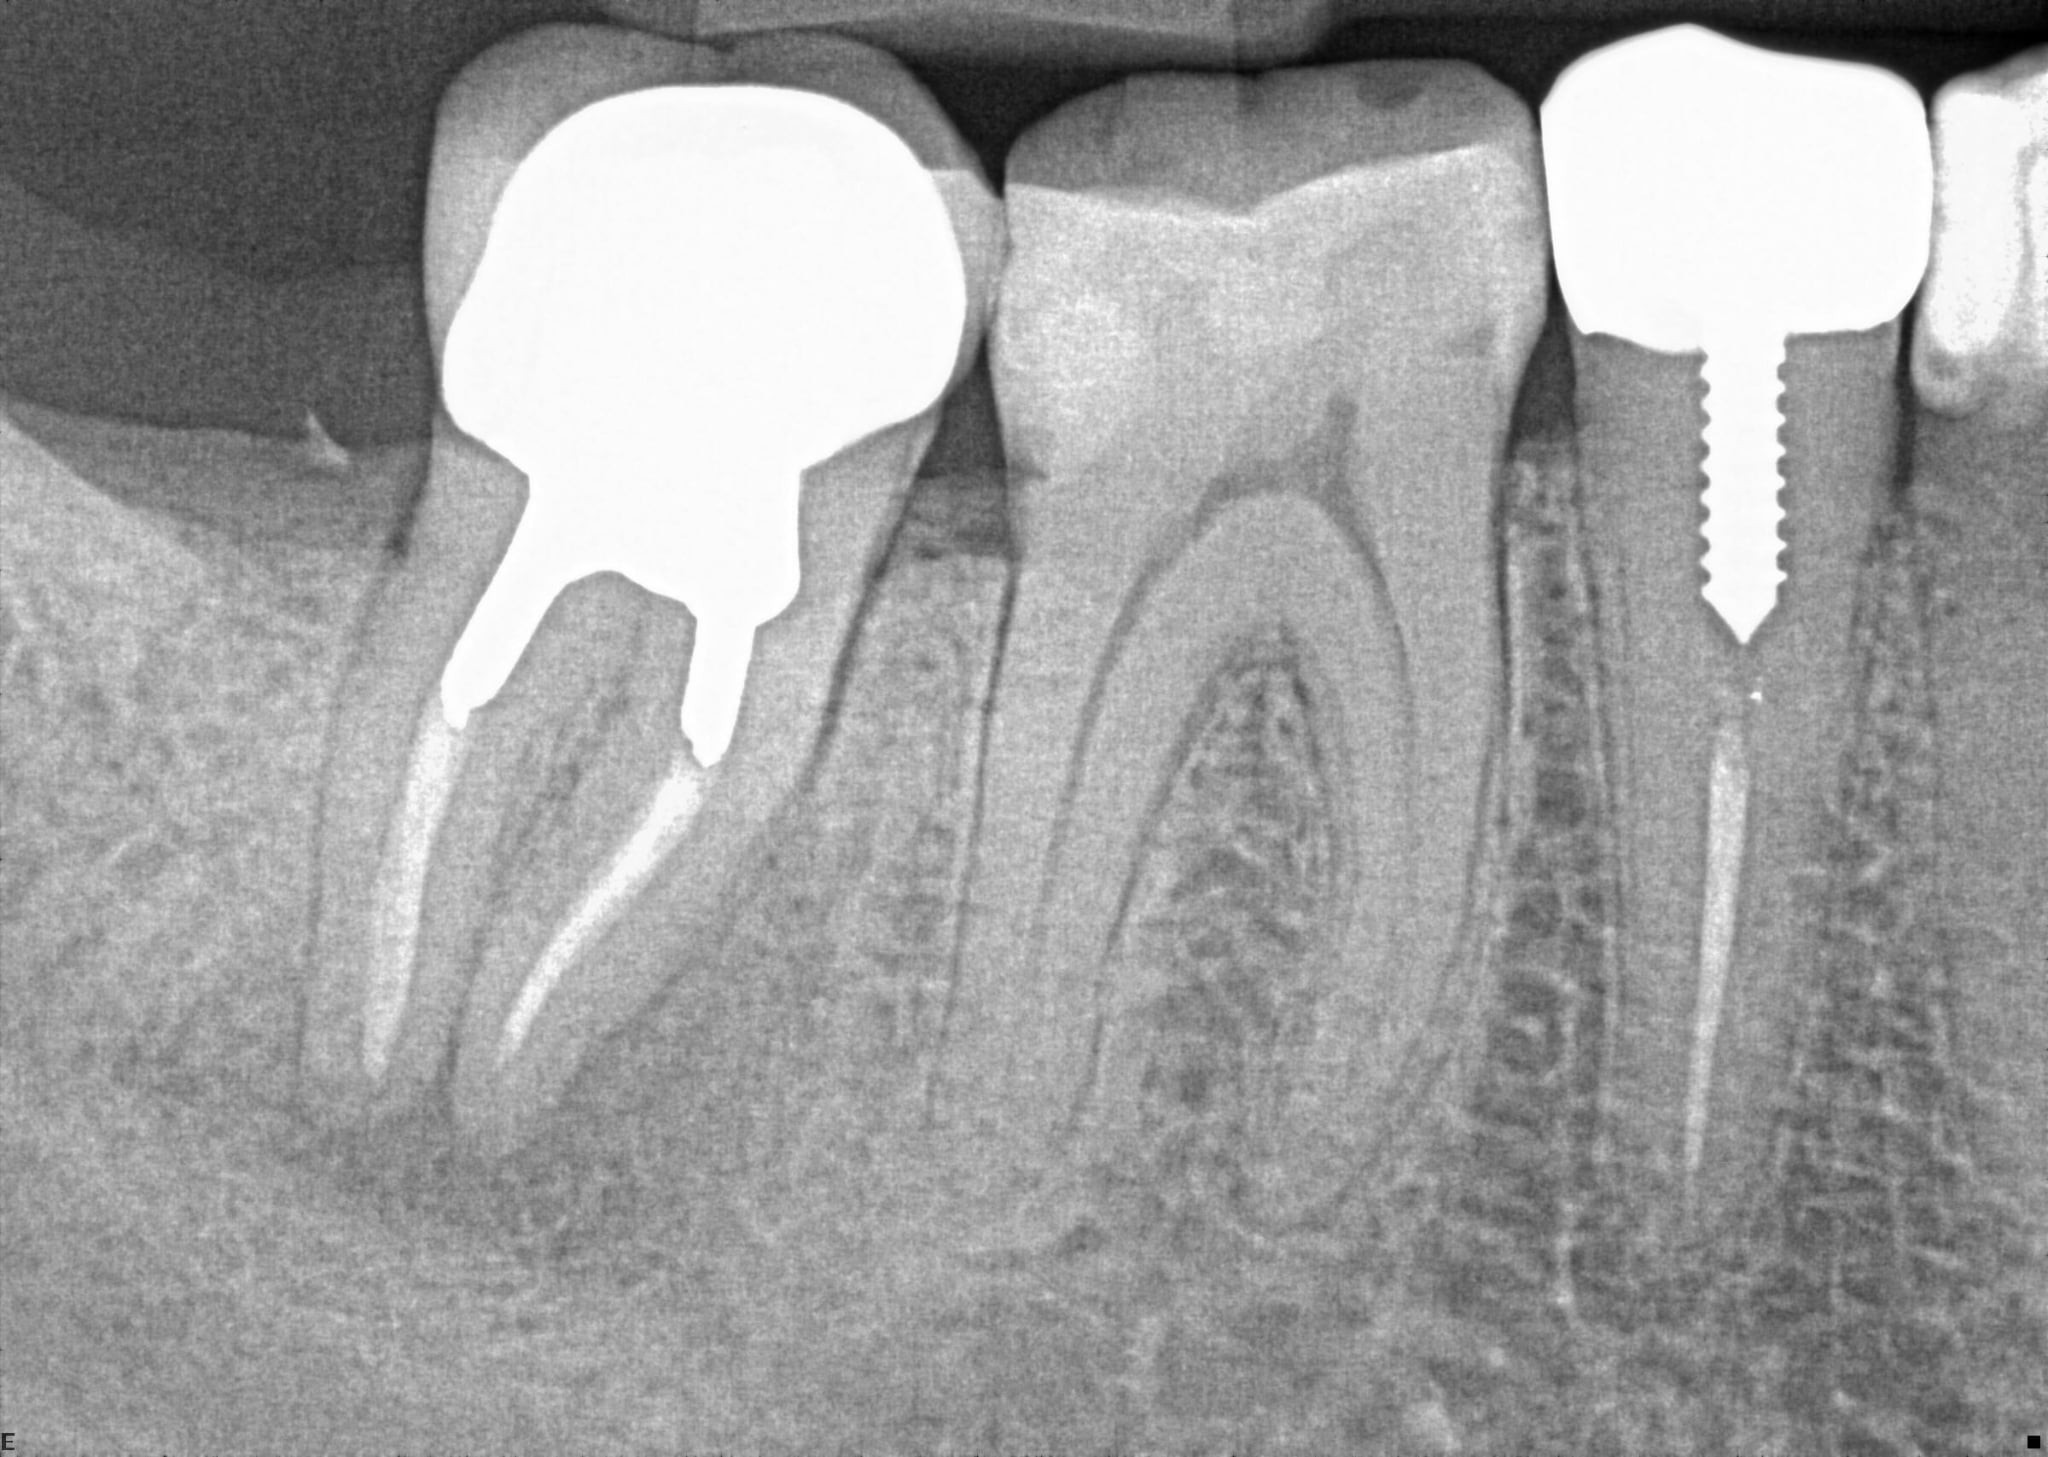

18. On which surface a recurrent caries can be detected?

crowns mostly show open margin not recurrent caries

19 / 35

19. On which surface a recurrent caries can be detected?

This is the PA X ray of the question # 18, based on this X ray recurrent X ray for distal tooth # 3.7 can also be selected